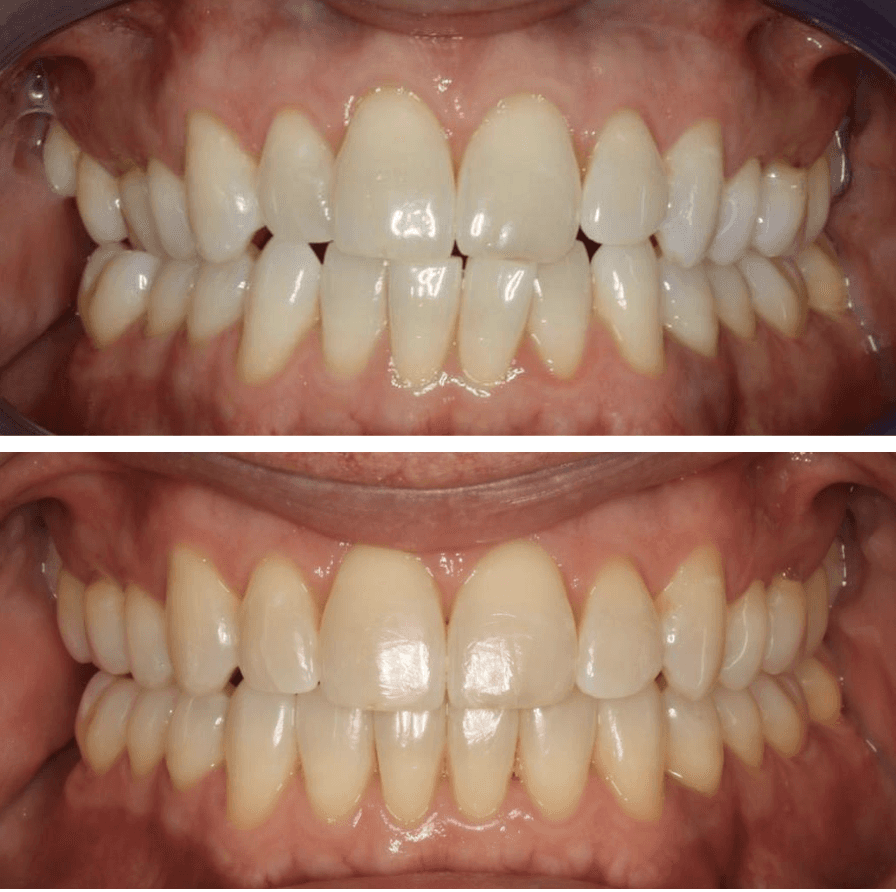

Diganosis: Minor and moderate crowding, anterior open bite, reverse smile arc, narrow maxilla, crossbite, tapered arch form

Adjuncts: Class III elastics, attachments, IPR

Initial treatment

INTRAORAL

Final results